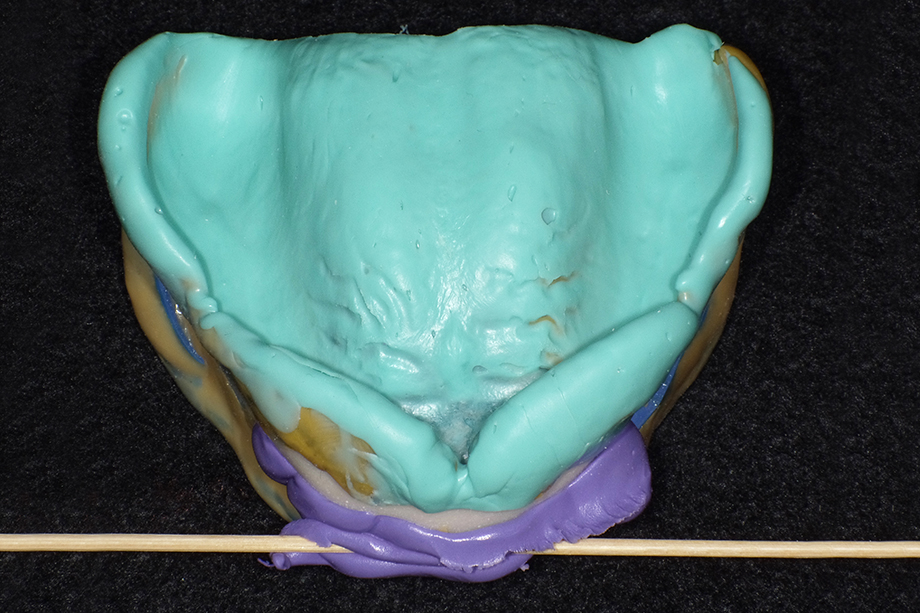

Klinischer Fall einer Totalprothese von Dr. Fumiaki Yamazaki mit der zahntechnischen Umsetzung von Toru Odagaki

1. Sprechen der Buchstaben: WOO – EEE

2. Bewegung der Zunge von einer Seite zur anderen

3. Schluckbewegung

4. Andrücken der anterioren Region beim Schließen des Mundes

Um die Saugeffizienz der Unterkieferprothesen zu optimieren, ist es essentiell, dass die Prothesenränder so gut wie möglich abschließen. Dies gewährleistet eine okklusale Stabilität der Prothese. Hierzu ist eine funktionale Form der konfektionierten Prothesenzähne wichtig.